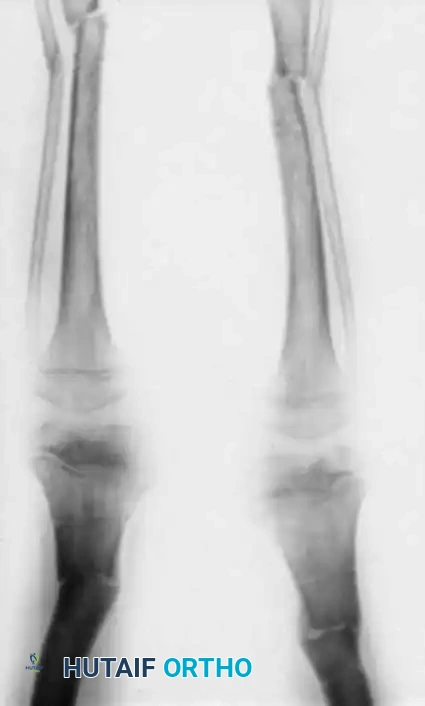

Image

Fig. 29-39 A, Preoperative standing radiograph of a child with vitamin D–resistant rickets demonstrating severe bilateral valgus deformities localized primarily to the distal femurs.

Fig. 29-39 B, Radiograph taken three months postoperatively following bilateral varus-producing osteotomies of the distal femurs and proximal tibias. Fixation was achieved using percutaneous pins incorporated into a plaster cast above and below the osteotomy sites.